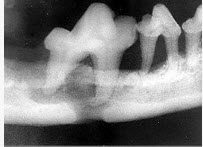

颌面外伤患者,咬合错乱,下唇麻木张口受限,经X线检查如图。应该为()

A、上颌骨骨折

B、颧骨骨折

C、颧弓骨折

D、下颌骨骨折

E、牙槽突骨折

D